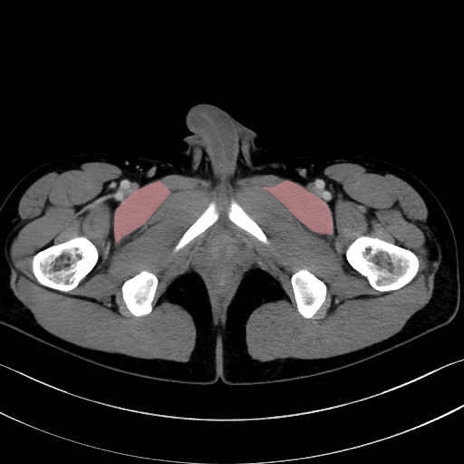

恥骨筋 (Pectineus)